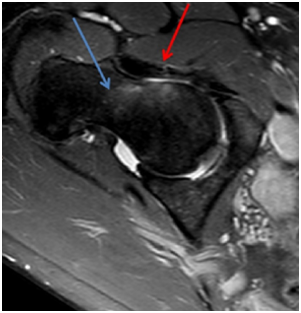

MRI shows injury of the superolateral aspect of the acetabular labrum, acetabular, femoral head and neck edema, joint effusion and partial tear of the iliofemoral ligament (Figures 1-3).

Figure 1 MRI in T2 SPIR sequence in the coronal section demonstrating labral lesion (red arrow) and partial rupture of the iliofemoral ligament (blue arrow).